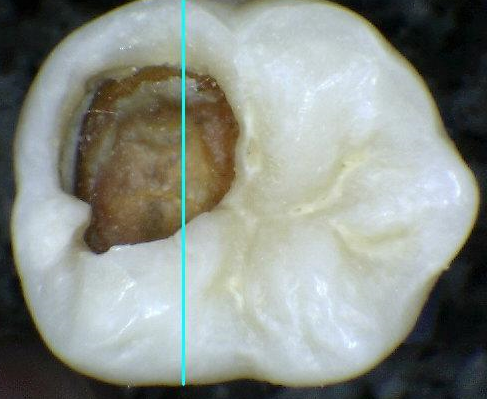

2. CÓDIGO 6

1. Cavidad extensa con paredes y piso en dentina.

1. DIAGNOSTICO DENTAL: CARIES CAVITACIONAL (ACTIVA / NO ACTIVA). Es activa cuando a la exploración clínica con cucharilla el tejido cariado se puede retirar acompañada de otros signos como encía enrojecida y presencia de sangrado, cuando es inactiva vemos que hay dentina reparativa de por medio, esta se ve opaca y no brillante.

1. TRATAMIENTO: Orientación en normas y educación de higiene oral al padre/madre/menor, control de placa, profilaxis, esta lesión puede comprometer la pulpa y consigo debe de realizar un tratamiento pulpar junto con una restauración ya sea en amalgama o composite, si esta lesión no es tan severa se retira la caries posterior a esto se realiza la reconstrucción de la pieza dental o si no hay mucho remanente se recurre a corona de acero en posteriores ó forma plástica en anteriores.